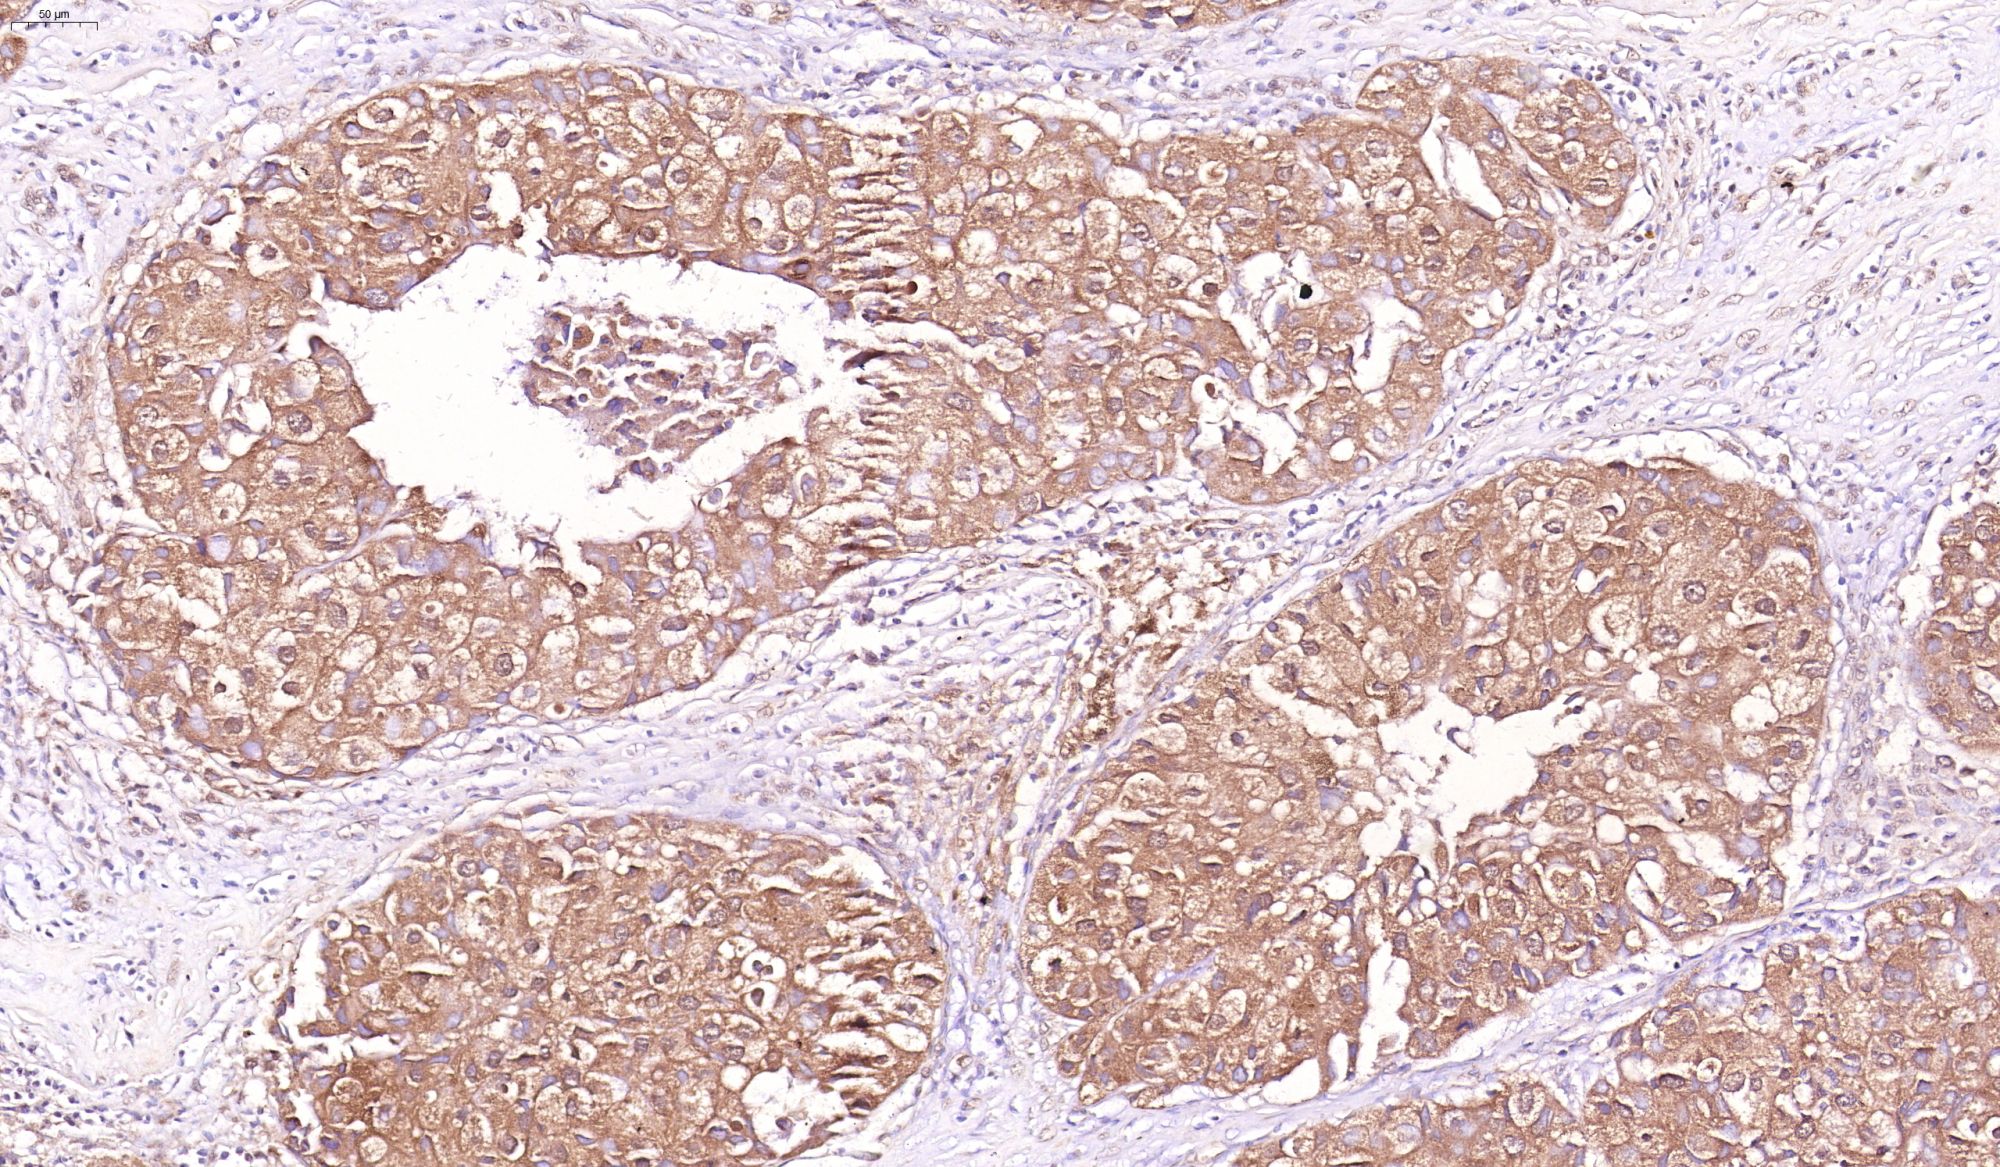

優(yōu)秀案例(免疫組化)